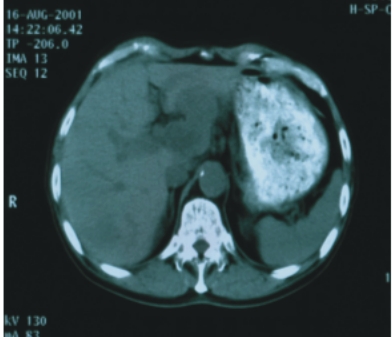

56歲/男性 (肝癌合併後腹腔淋巴腺轉移) |

74歲/男性 (直腸癌合併後腹腔淋巴腺轉移) |

||

| 90/5/2

(治療前) |

90/6/30(治療後) |

90/8/16(治療前) |

90/12/21(治療後) |